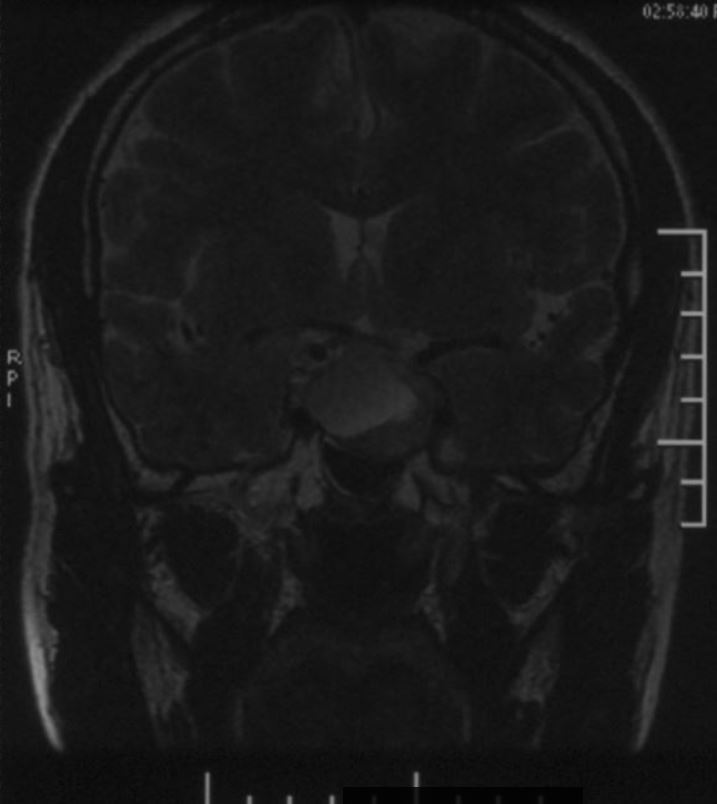

鞍区磁共振检查发现:鞍区肿瘤卒中可能,肿瘤侵犯双侧海绵窦、颈内动脉,鞍隔被顶起,鞍底部分塌陷。复旦大学附属肿瘤医院神经外科高阳

T2WI像